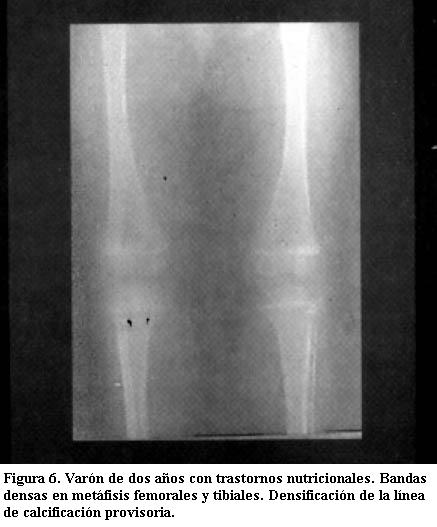

Densificación de la banda de calcificación provisional

Es una banda densa de espesor variable, que se observa con frecuencia en lactantes que tienen problemas nutricionales pasajeros que repercuten en el ritmo normal de crecimiento y formación del tejido óseo. Hay una falla pasajera en la actividad osteoblástica y se acentúa la calcificación provisoria (4).

Es semejante a la osteocondritis de primer grado y se plantea diagnóstico diferencial, pero en general no está afectado el peroné como en el saturnismo (figuras 6 y 7) (12).